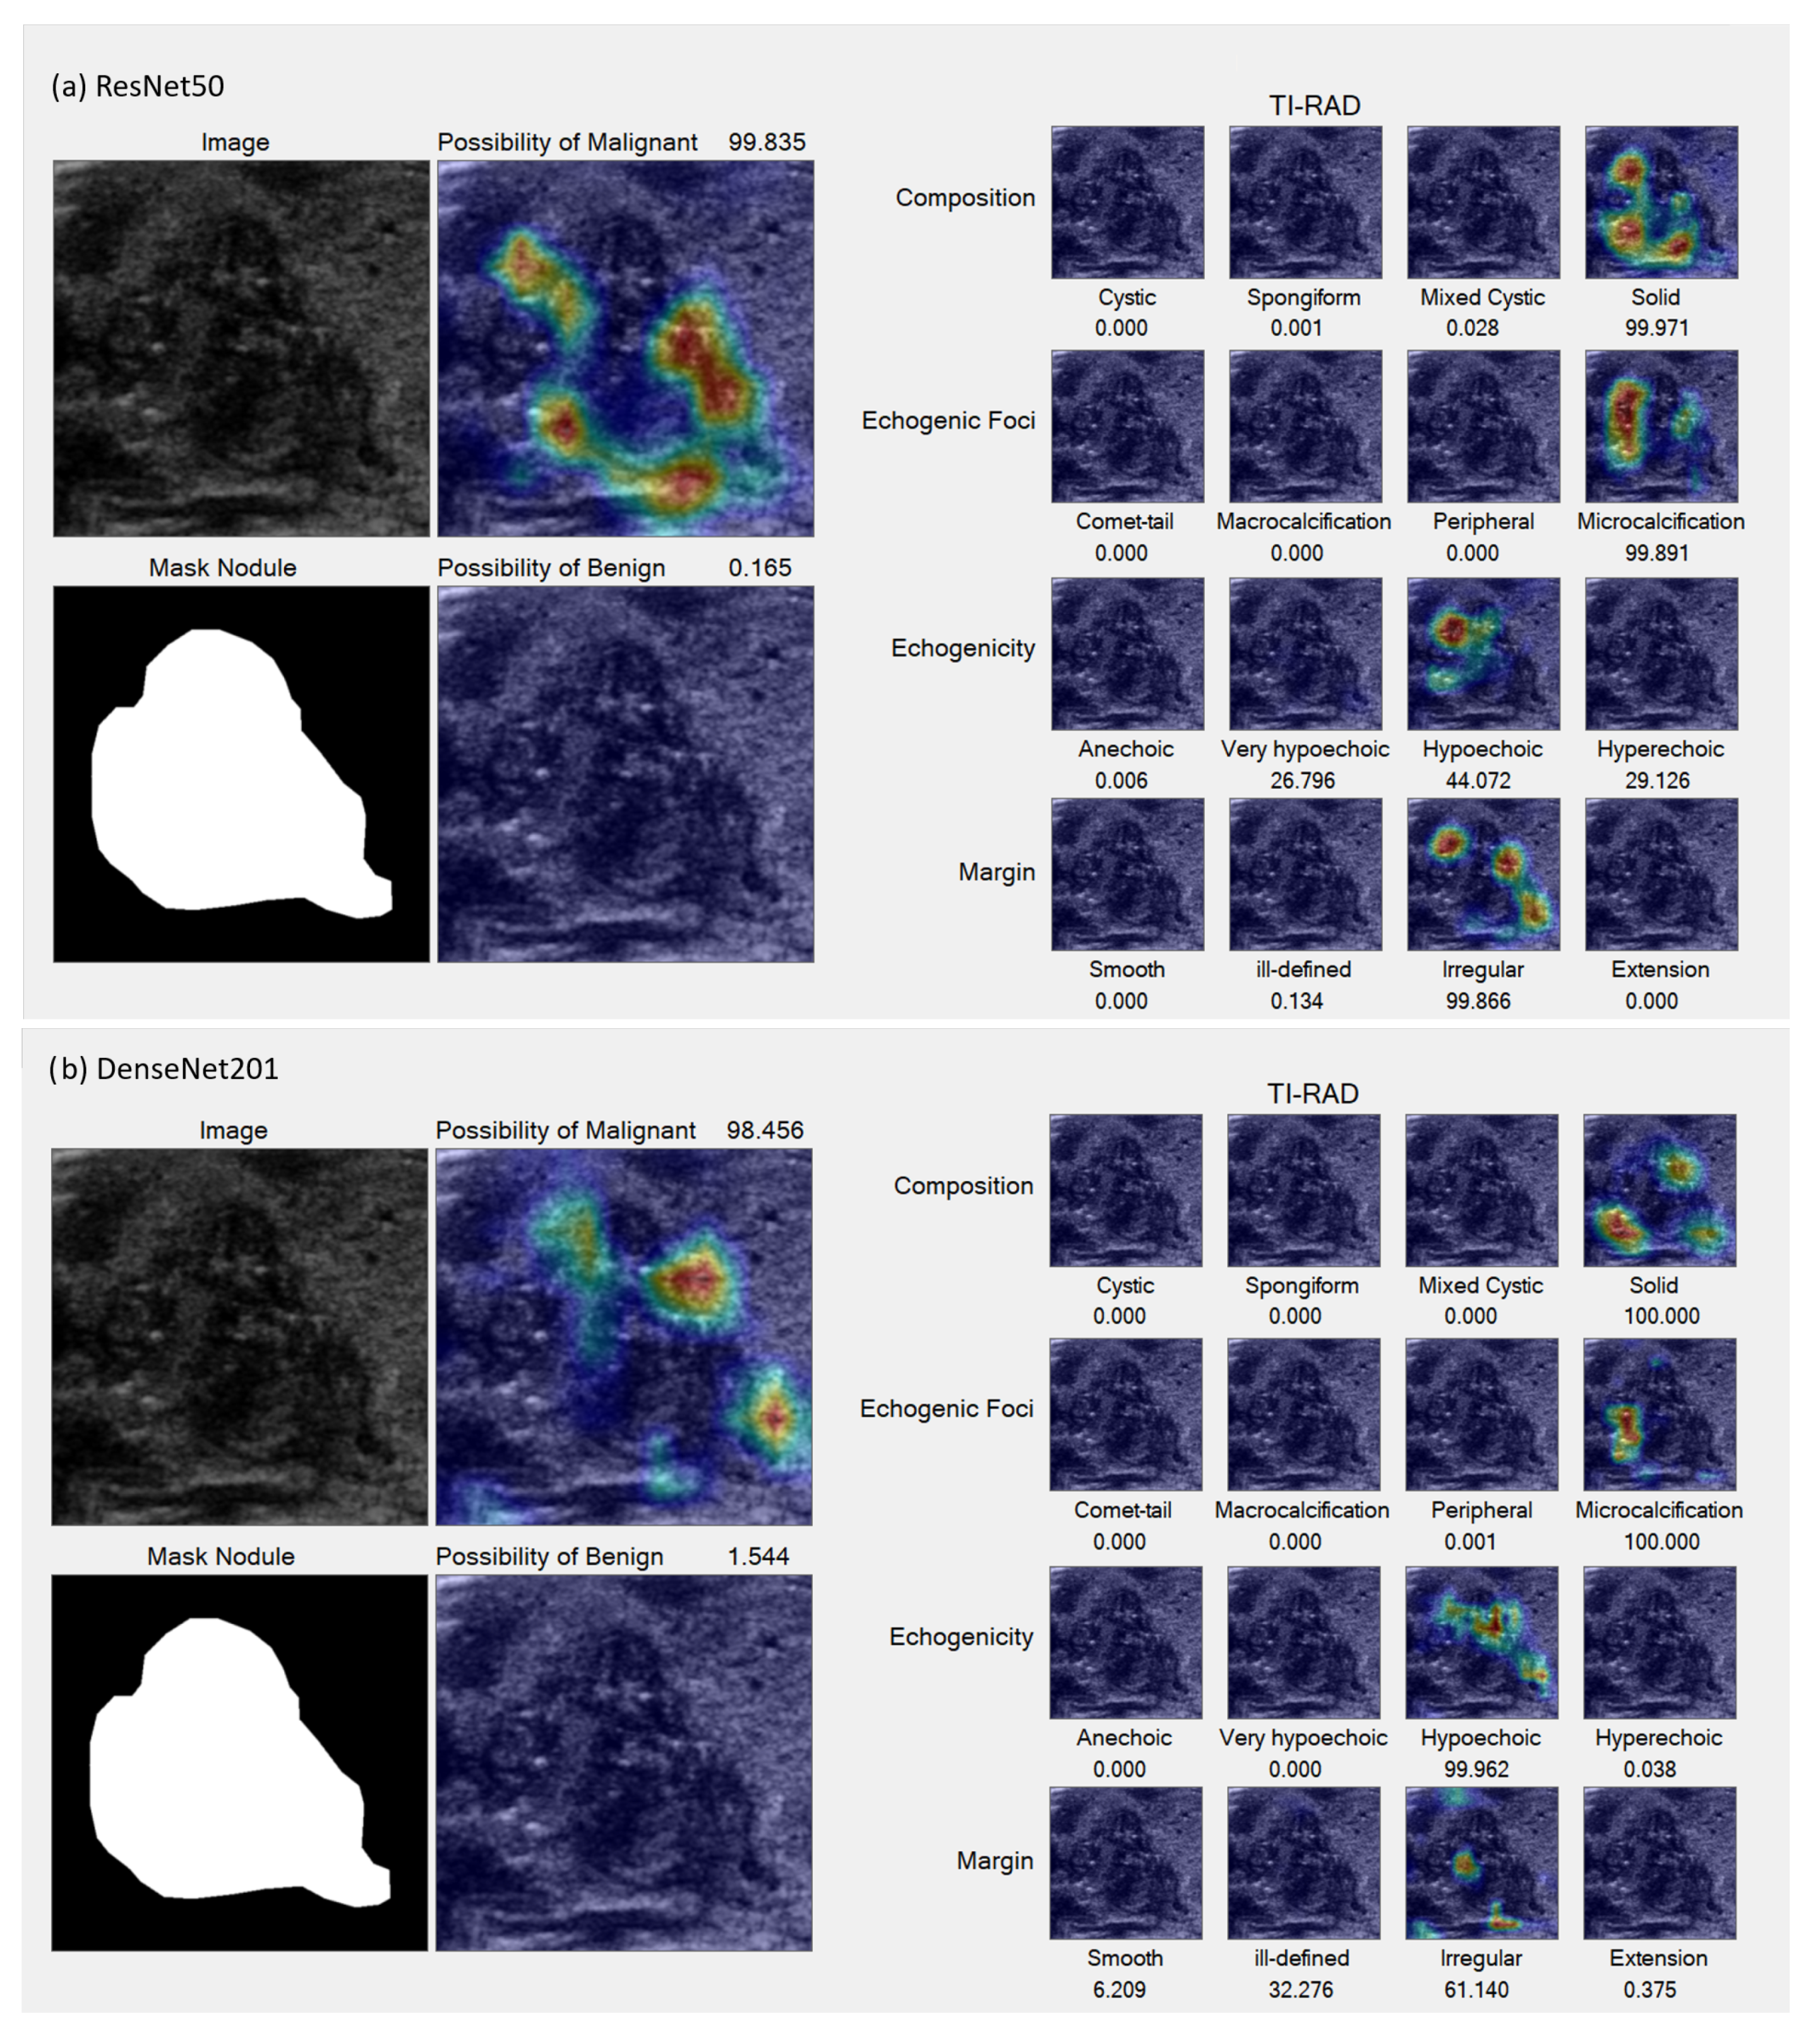

In the Grad-CAM visualization, we conducted individual analyses for each classification and sought the expertise of expert radiologists (coauthors DS and SB) to interpret the results.

Figure 7 and

Figure 8 present sample accurate outcomes along with corresponding expert explanations, while

Figure 9 displays a sample incorrect outcome and the experts’ interpretations for those cases.

This study seeks to investigate AI-driven analyses that simulate the cognitive process of radiologists, specifically evaluating discrepancies from the foundational principles outlined by the ACR TI-RADS guidelines. The Grad-CAM results underscore that the AI models’ analytical capabilities are largely congruent with the reasoning of radiologists. However, an exception was noted in the AI system’s inability to differentiate between micro-calcifications and macro-calcifications—distinctions typically made based on calcification size.

Figure 8.

Sample accurate results. (a,b) TI-RADS-5 malignant nodule characterized by hypoechoic composition, lobulated margins, internal micro-calcification, and a taller-than-wide appearance, all indicative of a high suspicion for malignancy (35%), which was subsequently confirmed pathologically. Both the ResNet50 (a) and DenseNet201 (b) models accurately identified the regions of micro-calcification and irregular borders. However, slight variations can be observed in the echogenicity and margin details between the two models.

Figure 8.

Sample accurate results. (a,b) TI-RADS-5 malignant nodule characterized by hypoechoic composition, lobulated margins, internal micro-calcification, and a taller-than-wide appearance, all indicative of a high suspicion for malignancy (35%), which was subsequently confirmed pathologically. Both the ResNet50 (a) and DenseNet201 (b) models accurately identified the regions of micro-calcification and irregular borders. However, slight variations can be observed in the echogenicity and margin details between the two models.